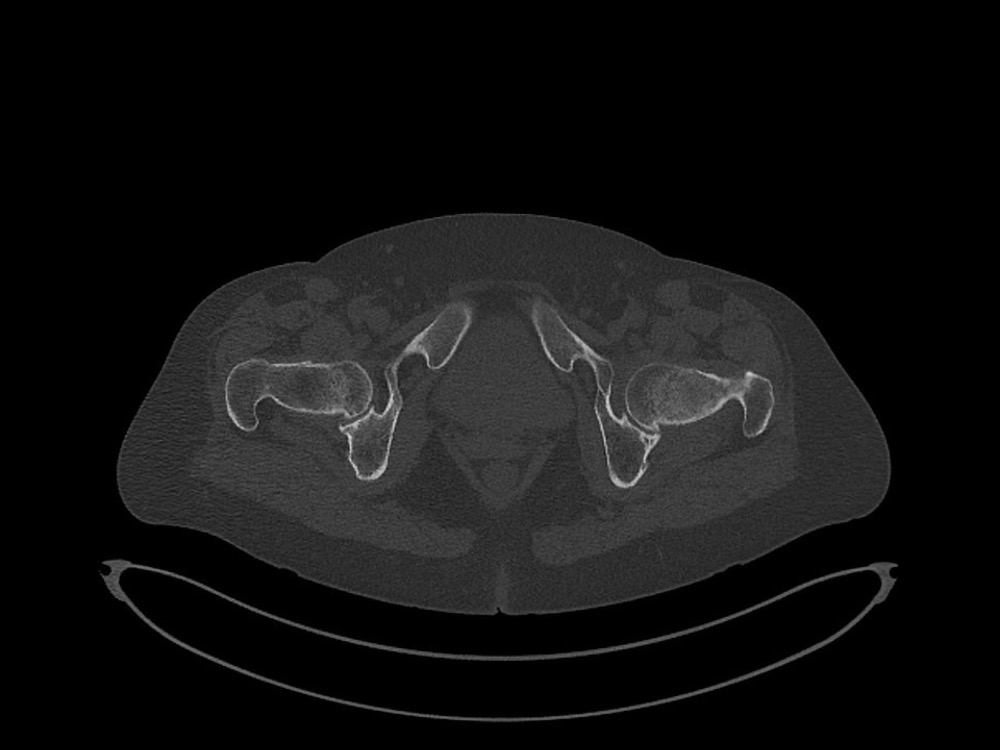

Douleurs de hanche

Linda Ouerd 06/11/2019